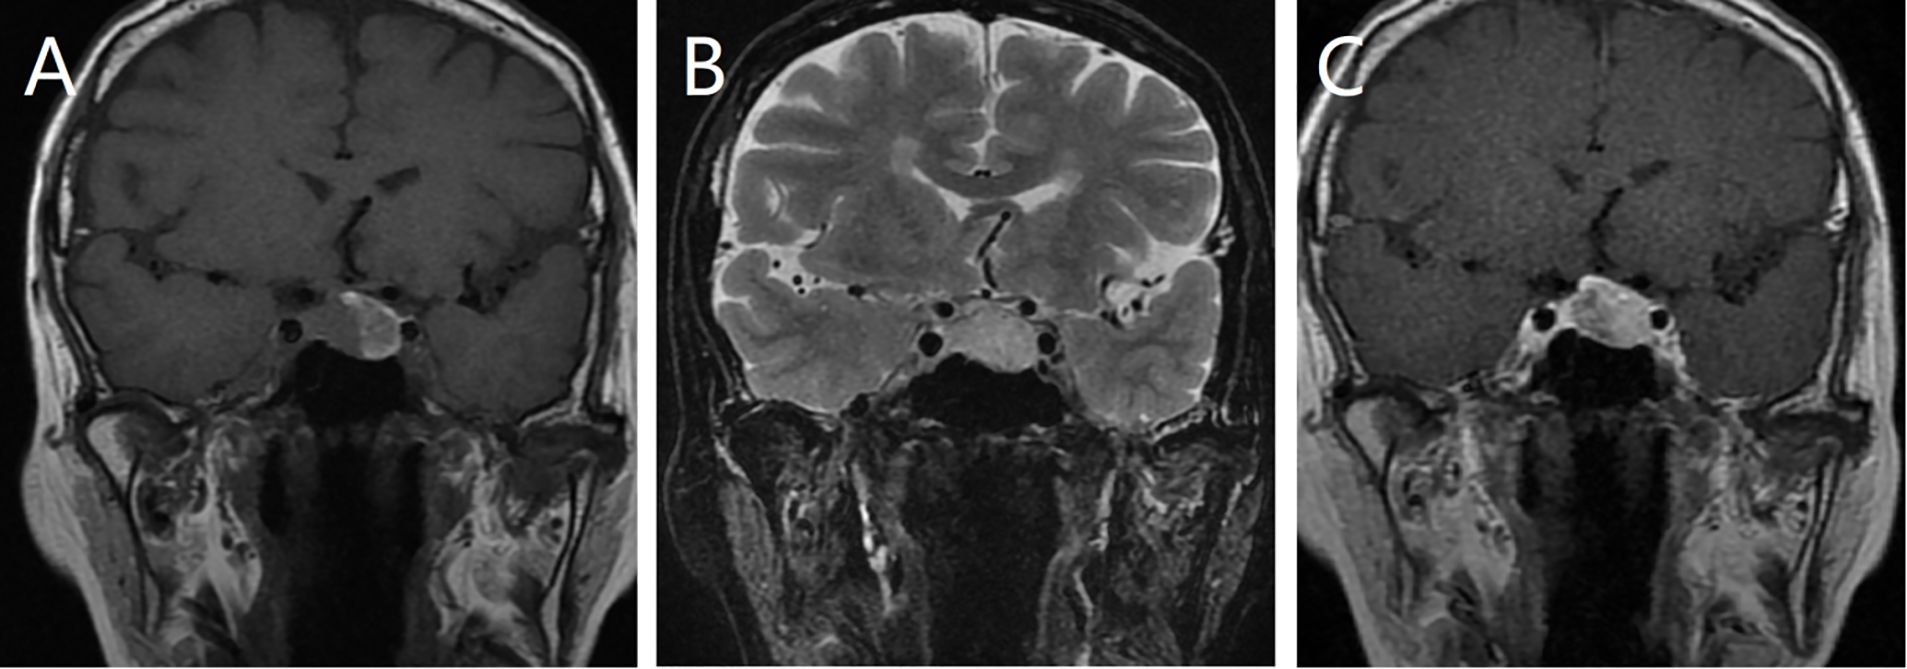

A 65-year-old female patient presented with a 5-month history of dizziness. Hormonal evaluation revealed abnormal cortisol levels of 66.93 nmol/L, 130.50 nmol/L, and 124.84 nmol/L at 0, 8, and 16 h, respectively, as measured using the electrochemiluminescence immunoassay method (reference range: 171.0–536.0 nmol/L). All other hormone levels were within the normal limits. Cranial magnetic resonance imaging (MRI) (Figure 1) showed a round, abnormal signal shadow in the left sellar region. T1-weighted imaging (T1WI) revealed isointense to slightly hyperintense signals, while T2-weighted imaging (T2WI) showed slightly hyperintense signals. The lesion had clear boundaries and measured approximately 1.7 × 1.5 cm (coronal measurement). Contrast-enhanced scans revealed progressive, uneven, and marked enhancement without evidence of sellar floor bone absorption or destruction. A preliminary diagnosis of pituitary macroadenoma was made.

Figure 1. Magnetic resonance imaging (MRI) scans showing a circular abnormal signal shadow on the left side of the sellar area. The lesion exhibits an equal to slightly higher signal on T1-weighted imaging (T1WI) (A) and a slightly higher signal on T2-weighted imaging (T2WI) (B), with clear boundaries. Contrast-enhanced MRI showing progressive inhomogeneous enhancement (C).

The MRI features of MM with pituitary metastasis are dynamically influenced by melanin content owing to its paramagnetic properties. Melanin-rich tumors typically exhibit T1WI hyperintensity and T2WI hypointensity. In our case series, 38.9% (7 out of 18) of cases exhibited this typical “T1 hyperintensity/T2 hypointensity” pattern, while the present case displayed atypical slight T2 hyperintensity, likely related to a lower melanin content. These MRI features are closely associated with the pathological characteristics of MM, reflecting its growth and metabolic features within the pituitary gland. However, similar MRI features can also be observed in hemorrhagic pituitary macroadenomas (12, 37), making preoperative diagnosis challenging and necessitating close integration with clinical history.